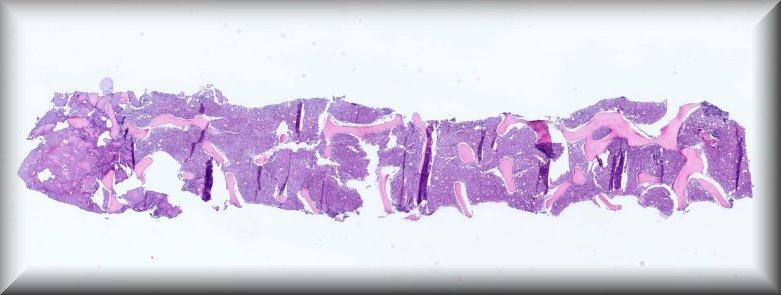

Caso 2.- Roger Eduardo Casco Zuniga; Evelyn Beatriz Troncoso Hernández; Svetlana Shalygina; Paola Andrea Chilito Paredes; José Luis Losa García.

Hospital General Universitario de Alicante.

Varón de 79 años, con antecedente de mieloma múltiple en actual tratamiento. Acude a servicio de urgencias por astenia de 4 días de evolución y presencia de pancitopenias persistente a pesar de tratamiento. Se realiza biopsia de médula ósea en el que se observa infiltración difusa por células pequeñas de estirpe linfoide y un 15% aproximado de células plasmáticas con restricción de cadenas ligeras Kappa.